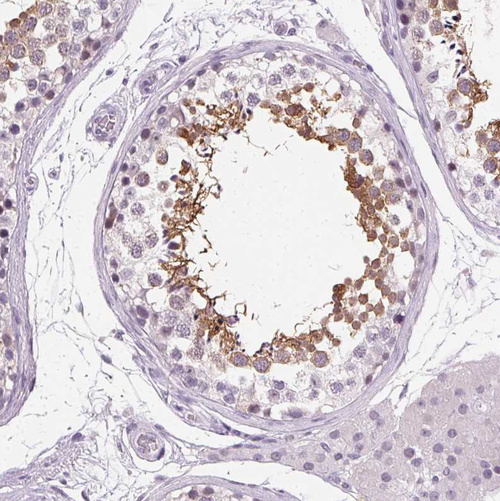

Immunohistochemistry analysis in human testis and prostate tissues using HPA041830 antibody. Corresponding ROPN1L RNA-seq data are presented for the same tissues.